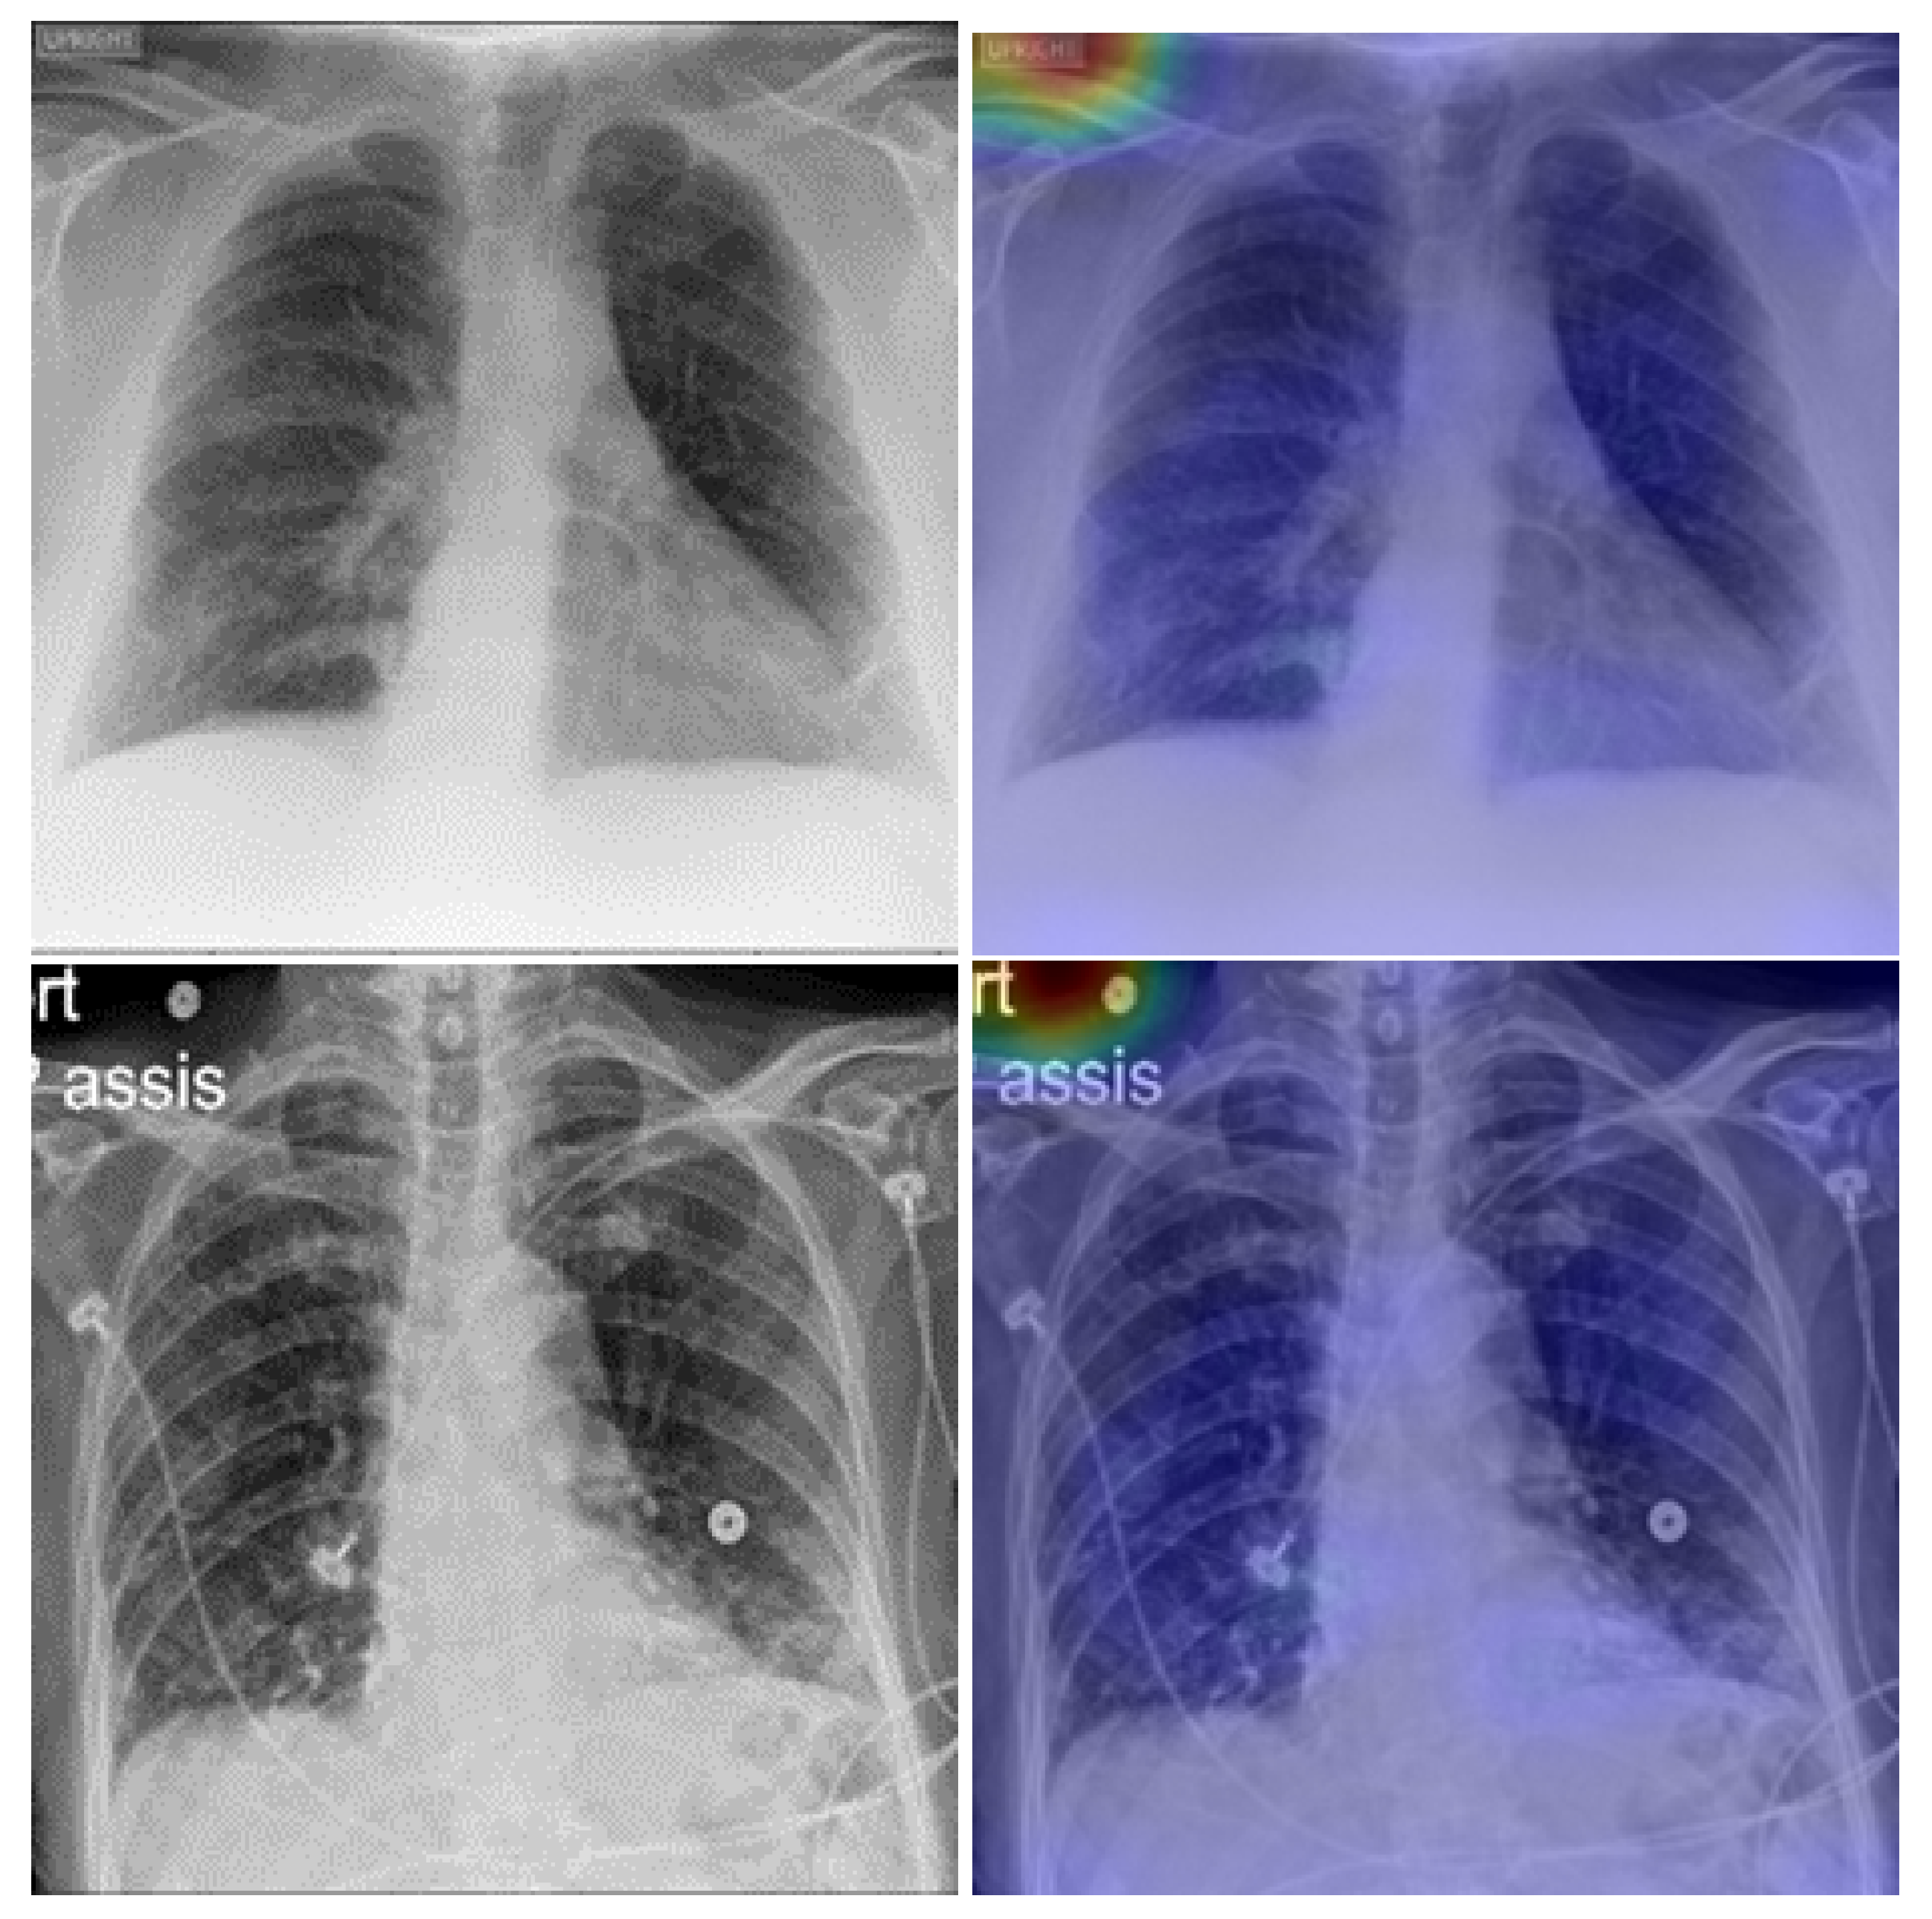

5. Model Explainability